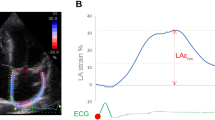

LA strain and strain rate (SR) were acquired using Medis (version 4.0.24, Medis Medical Imaging Systems, Leiden, the Netherlands) post-processing software analysis. The LA endocardial border was manually traced on two- and four-chamber cine images (the presence of pulmonary veins or corresponding segments of the left heart ear were excluded from analysis). A final visual review was performed to ensure accurate tracking of the atrial myocardium. If the automatic boundary tracking was not accurate, the initial contours were manually adjusted and the algorithm was then reapplied (Fig. 1).

LA strain parameters include global longitudinal strain (GLS) and global circumferential strain (GCS). The LA GLS includes reservoir strain (GLS reservoir, corresponding to the atrial reservoir function), conduit strain (GLS conduit, corresponding to the atrial conduit function), and booster strain (GLS booster, the atrial systolic booster pump function). Consequently, three LA GLS SR parameters were derived: SR reservoir (positive strain rate), SR conduit (early negative strain rate), and SR booster (late negative strain rate). LA strain and strain rate were evaluated from 2-chamber and 4-chamber cine images and the average values were calculated.The presence of LGE was visually assessed by two independent observers (DT and ZYL) who were blinded to the clinical data. The post-processing software Medis (version 4.0.24, Medis Medical Imaging Systems, Leiden, the Netherlands) was used for LGE image analysis. The LGE was quantified using the six standard deviations (SD) from the normal myocardium signal intensity and expressed as LGE extent and LGE mass.